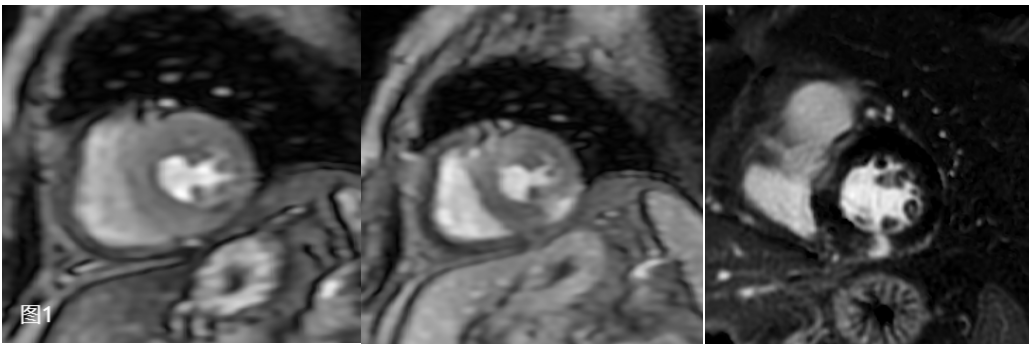

患者为一名60岁女性患者,因主诉“心前区疼痛5天”入院,患者为压榨性疼痛,伴胸闷、气短,休息后不能缓解。查心电图示窦性心律,ST-T段改变,肌钙蛋白超过2000pg/ml,临床考虑急性非ST段抬高型心肌梗死,入院冠状动脉DSA证实患者管腔前降支狭窄约50%,经心血管内科张岩副主任仔细分析患者病情,建议患者行药物负荷心肌磁共振灌注成像明确诊断。11月20日晚在大明宫院区,医学影像科丁墩副主任指导,徐增苗技师优化扫描序列,在患者有幽闭情绪的情况下,顺利使用瑞加诺生进行负荷MR心肌灌注成像,注射药物后1分钟后患者心率由70次/分上升至最高95次/分,扫描过程中严密监视患者心率及不良反应,随后顺利完成心脏电影、心肌延期增强扫描,患者自觉无任何其他不适,检查顺利完成。

经负荷心肌灌注显像提示患者左心室多节段可见心内膜下灌注缺损,延迟强化提示下壁透壁性心肌梗死,经磁共振心脏成像诊断为MINOCA,这也解释了患者心外膜冠状动脉主要分支未见明显狭窄,仍反复出现胸闷、胸痛等症状。目前患者经治疗,病情平稳顺利出院。

磁共振负荷心肌灌注成像增加了心肌微循环障碍患者的检出率,同时通过后处理软件对延迟强化可进行定量及半定量分析。因此负荷心肌灌注成像可应用于冠状动脉交界性狭窄患者、冠状动脉狭窄<50%的患者以及非缺血性心肌病患者,评估其是否存在微循环障碍,是目前诊断心肌微循环障碍的金标准,为心内科医生对这类患者采取个性化治疗方案提供客观依据,并可进行疗效评价。